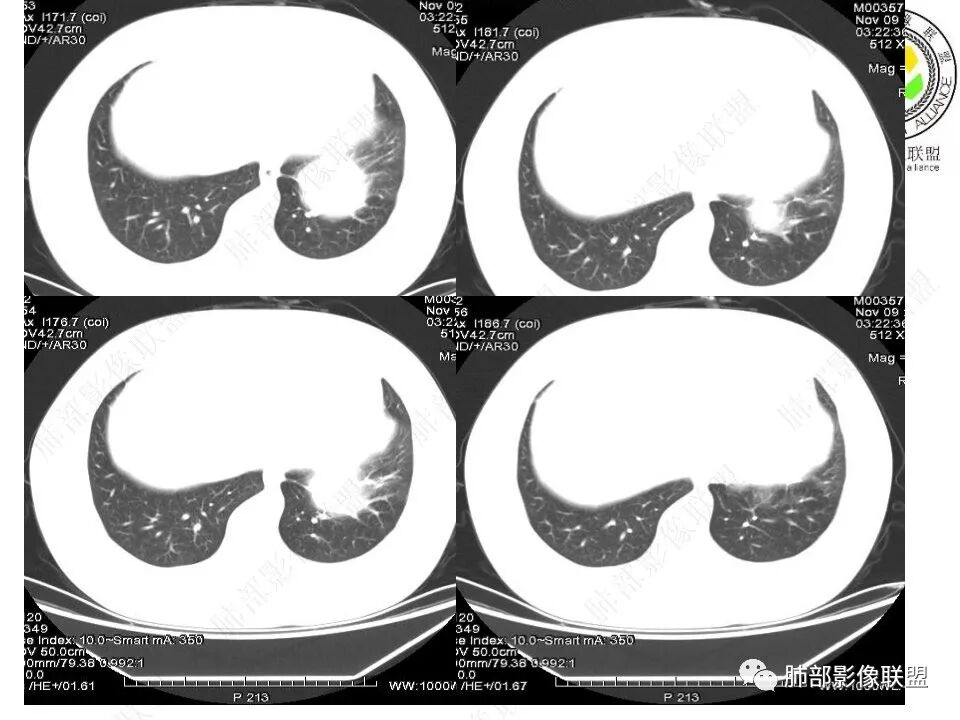

我将内部结构再重建一下

下肺静脉:

还是肺动脉供血,肺静脉引流

青年男性,体检发现左肺不规则类圆形占位性病变,叶间裂区域,定位胸膜来源。左肺下叶支气管受压狭窄,但管壁光整,未见腔内阻塞或管壁受侵。包块边界清晰,浅分叶,内部密度不均匀,病灶后份见空气新月征。渐进性强化,增强动脉期见分支状血管,蛇纹血管征。肺门纵膈未见增大淋巴结,符合孤立性纤维瘤(SFT)。